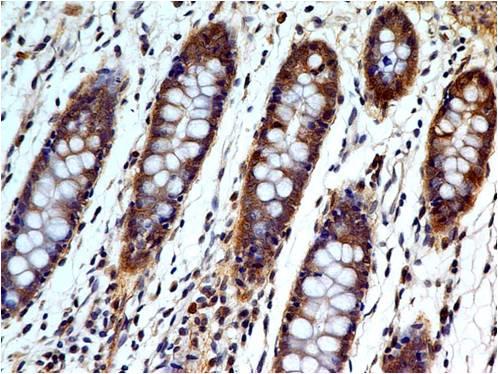

Follicle-Stimulating Hormone (FSH) allows for progression of ovarian folliculogenesis, and enables Sertoli cell proliferation in the testis. Anti-FSH reacts with FSH-producing cells, therefore FSH staining is useful for classifying pituitary cancers and understanding pituitary disease.

Recommended dilutions: Immunohistochemical analysis: 1:100 - 1:200. However, this need to be optimized based on the research applications.